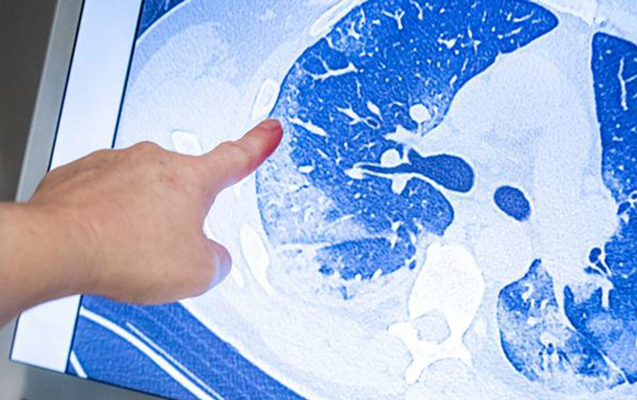

O qeyd edib ki, əgər ciyərlərin 50-70 faiz zədələnməsi baş verərsə, orada fibroz toxumanın inkişaf etməsi qaçılmazdır: "Xəstəlik həmin şəxslərdə öz izini qoyur. Xüsusən yaşlı insanlarda buna rast gəlinir. Çünki həmin şəxslərin immun sistemi zəif olur, yanaşı xəstəlikləri olur. Sağ qalsa belə, cavanlara nisbətən onun bərpa olma imkanları daha azdır”.